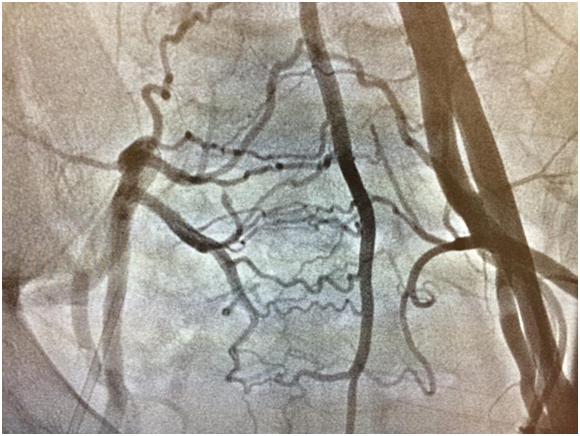

Xəstəyə ürək boşluqlarının kateterizasıyası qərarı verildi. Kateterizasiya zamanı sağ femoral arteriyanı punksiya məqsədilə palpasiya etdikdən nəbz qeyd edilmədi. Bu səbəbələ xəstənin sol femoral arteriya və venası punksiya olundu. Ürək boşluqları kateterizasiya olundu və xəstənin inoperabel olduğu qərarı verildi. Sağ femoral arteriyada nəbz qeyd olunmadığından xəstəyə abdominal aortaqrafiya olundu. Aortoqrafiya zamanı xəstənin sağ ümumi, daxili və xarici qalça arteriyalarının olmaması, aortanın bifurkasiya nahiyəsinin və sol ümumi qalça arteriyasının başlanğıcının fibromuskular distrofiyaya məruz qalması və sağ aşağı ətrafın sol daxili qalça, orta oma arteriyalarından gələn anastamozlar vasitəsilə qidalandığı aşkar edildi. Xəstə asimptomatik idi. Bu səbəbdən təqib qərarı verildi, heç bir müdaxilə olunmadı. (Şəkil 4,5,6)

Kollateral arteriyaların aşkar müşahidə olunması, sağ qalça arteriyasının güdülünün olmaması və xəstənin cavan olması müşahidə etdiyimiz patologiyanın anadangəlmə olduğuna dəlalət edir. Sağ ümumi qalça arteriyanın olmaması bu xəstədə asimptomatikdir, lakin gələcəkdə kollateral arteriyalar aterosklerotik dəyişikliklərə məruz qalarsa və ya FMD daha da irəliləyərsə xəstə simptomatik ola bilər.Finromuskular displaziyanı və sağ qalça arteriyasının olmamasını qalça arteriyanın aterosklerotik obliterasiyası, vaskulit, seqmental arterial mediolizis, requlyar arterial dalğalardan və Takayasu arteriitindən differensasiya etmək lazımdır.